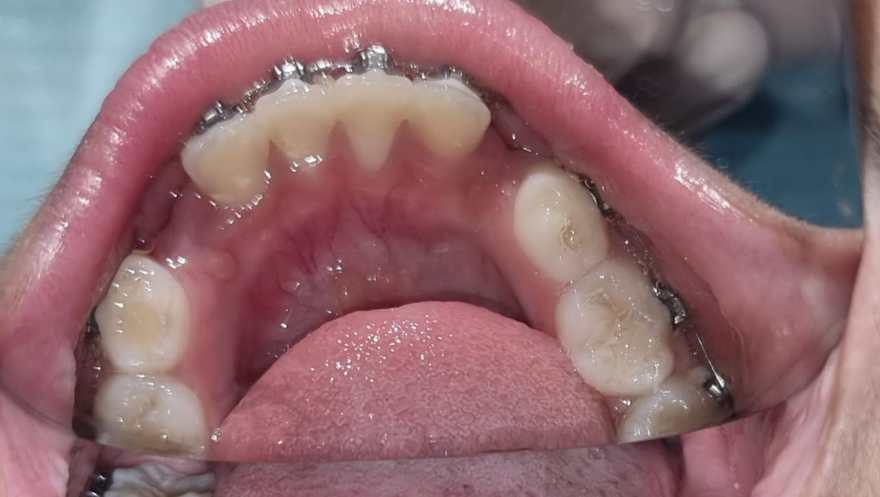

37) Jad – Upper and lower crowding and both laterals are palatally placed. – Upper treatment is completed.